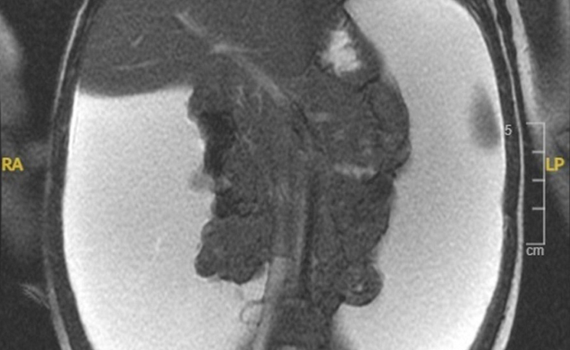

¿Cuál es su diagnóstico?

Imagen de la semana